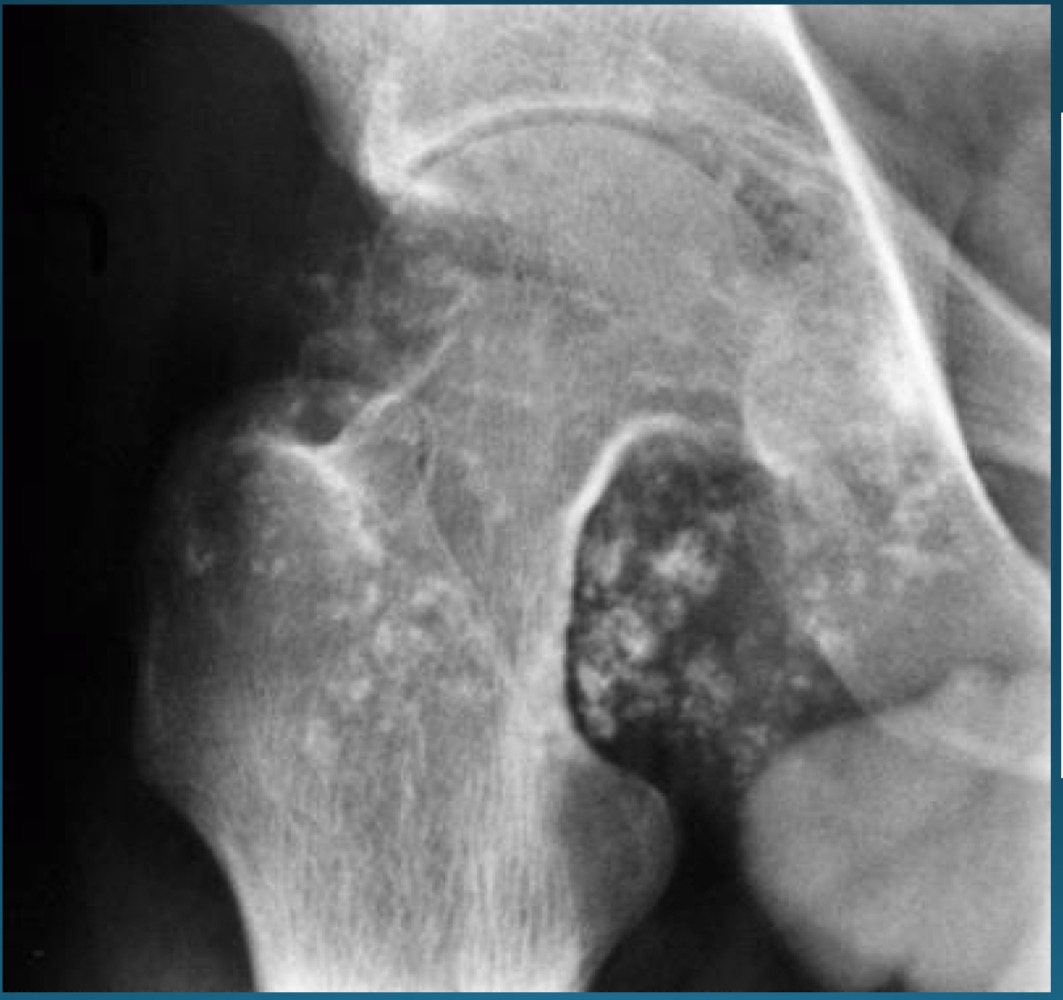

what is this finding?

synovial chondromatosis (SCM)

what is the most commong site for synovical chrondomatosis

knee

loose bodies from synovial chondromatosis might predispose the patient to?

degenerative osteoarthritis

what do you call this feature? what diagnosis is this part of ?

apple core deformity, synovial chondromatosis